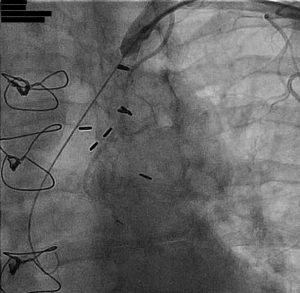

Catheter based interventions for pulmonary embolism is on the rise. The rise in mainly in patients who present with submassive PE. The intent of intervention is to reduce clot burden. This is done to improve acute symptoms and to reduce long-term complications. A common intervention for pulmonary embolism is infusion of thrombolytics. This can be…